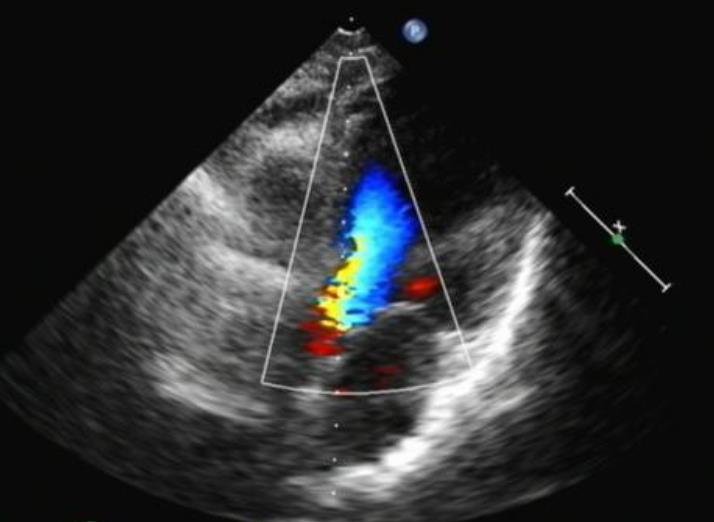

心脏超声

• 肺动脉收缩压正常高值,肺动脉瓣轻度反流

• 三尖瓣轻-中度反流

• 二尖瓣、主动脉瓣轻度反流

• EF=59% 、 FS =31%